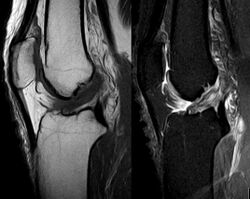

Though clinical examination in experienced hands can be accurate, the diagnosis is usually confirmed by magnetic resonance imaging, which provides images of the soft tissues like ligaments and cartilage around the knee.[1] It may also permit visualization of other structures which may have been coincidentally involved, such as the menisci or collateral ligaments.[30] An x-ray may be performed in addition to evaluate whether one of the bones in the knee joint was broken during the injury.[9]

MRI is perhaps the most used technique for diagnosing the state of the ACL, but it is not always the most reliable technique as the ACL can be obscured by blood that fills the joint after an injury.[31]

MRI is particularly useful in cases of partial tear of the ACL. The anteromedial band is most commonly injured compared to the posterolateral band.[32]